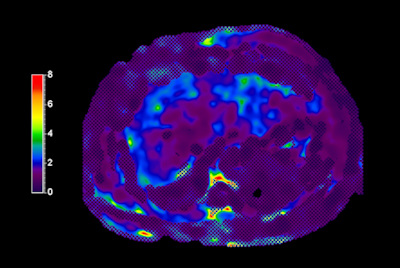

Breast Ca with T1 perfusion